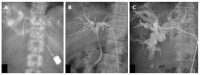

Hilar cholangiocarcinoma is a common malignant tumor of the biliary tree. It has poor prognosis with very low 5-year survival rates. Various imaging modalities are available for detection and staging of the hilar cholangiocarcinoma. Although ultrasonography is the initial investigation of choice, imaging with contrast enhanced computed tomography scan or magnetic resonance imaging is needed prior to management. Surgery is curative wherever possible. Radiological interventions play a role in operable patients in the form of biliary drainage and/or portal vein embolization. In inoperable cases, palliative interventions include biliary drainage, biliary stenting and intra-biliary palliative treatment techniques. Complete knowledge of application of various imaging modalities available and about the possible radiological interventions is important for a radiologist to play a critical role in appropriate management of such patients.We review the various imaging techniques and appearances of hilar cholangiocarcinoma and the possible radiological interventions.